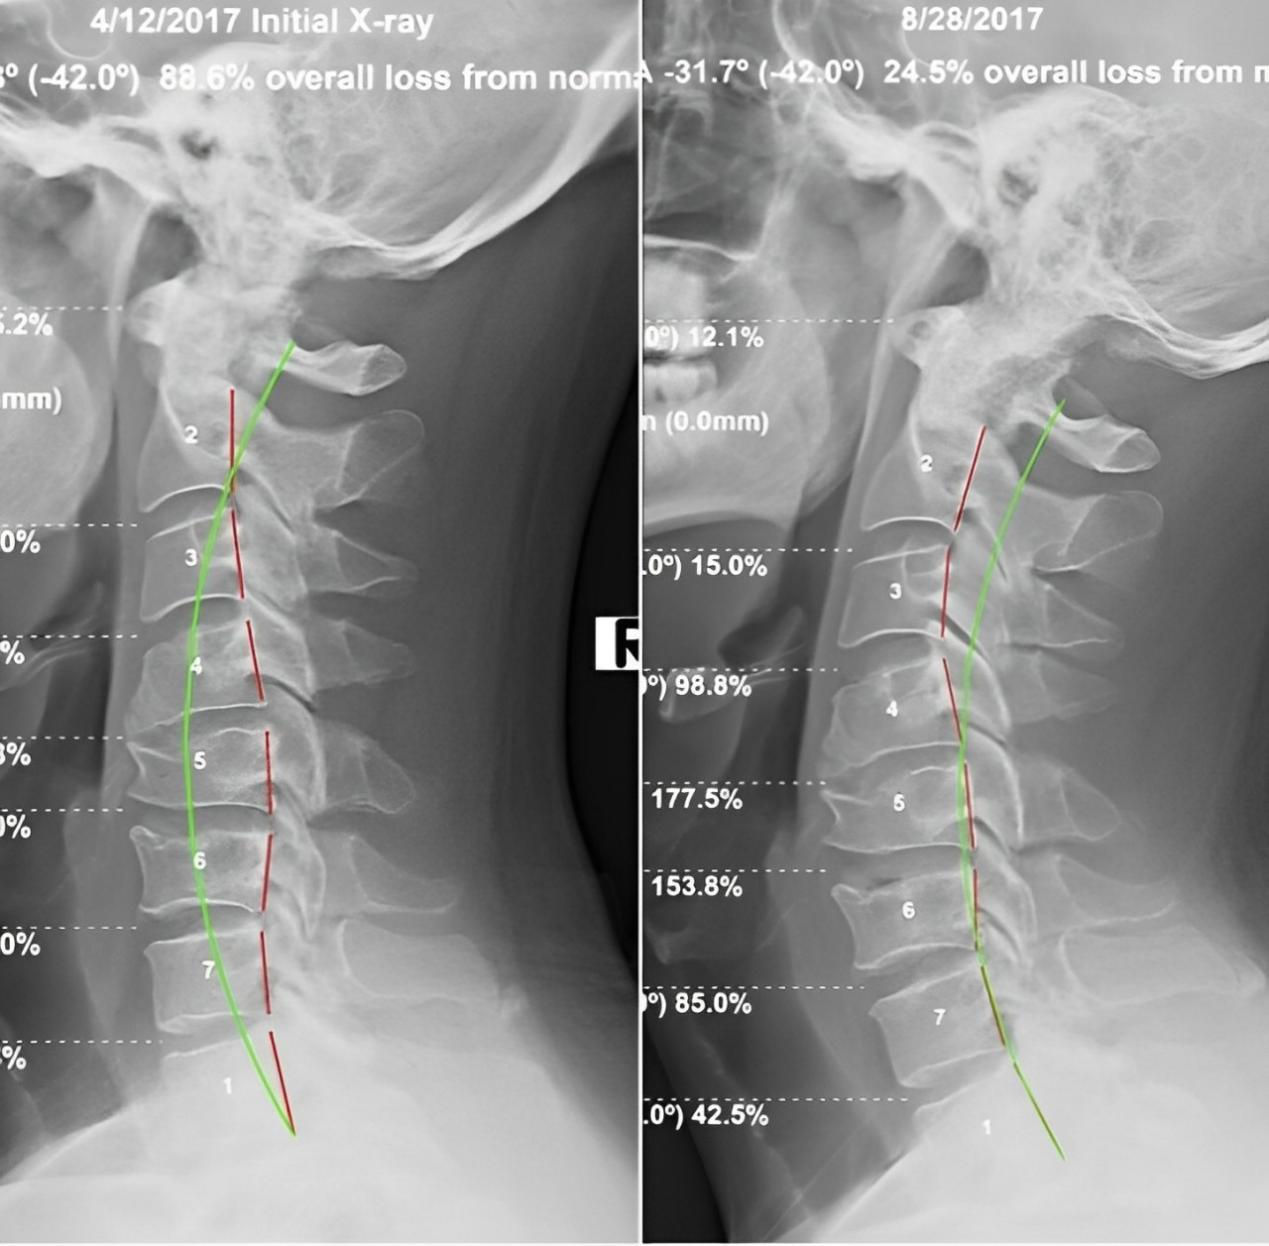

四、 恢復脊椎自然曲度

五、矯正完和矯正后的對比案例: